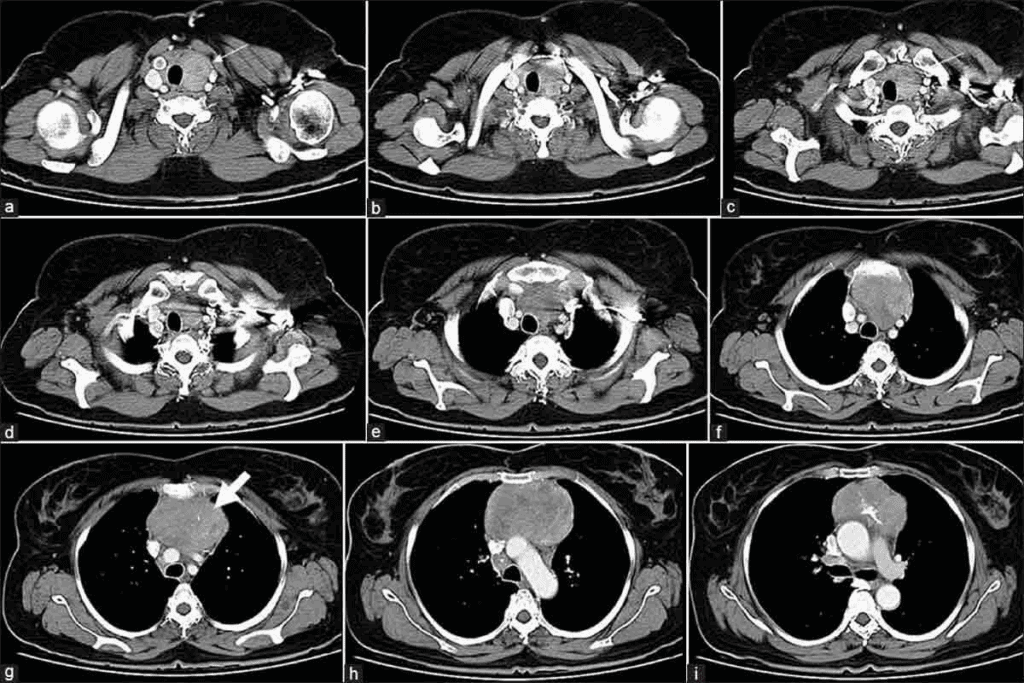

How CT Technology Creates Detailed Cross-sectional Images

Chest CT scans combine X-rays and computer tech for detailed images. An X-ray tube moves around the body, taking many pictures. These pictures are then put together into a 3D image.

This image shows the chest’s inside parts clearly. It includes soft tissues, blood vessels, and lungs.

It’s great at showing soft tissues and areas around the lungs and heart. This helps spot problems that X-rays can’t see.

Detailed Visualization Capabilities of Chest CT Scans

Chest CT scans give us a clear view of the chest area. This helps doctors make accurate diagnoses and plan treatments. Our team uses the latest CT technology to get high-quality images. These images help in managing different chest conditions.

Soft Tissue Visualization and Analysis

Chest CT scans are great at showing soft tissues in detail. This is key for spotting problems like tumors, infections, and inflammation. Our radiologists study these images closely to give correct diagnoses.